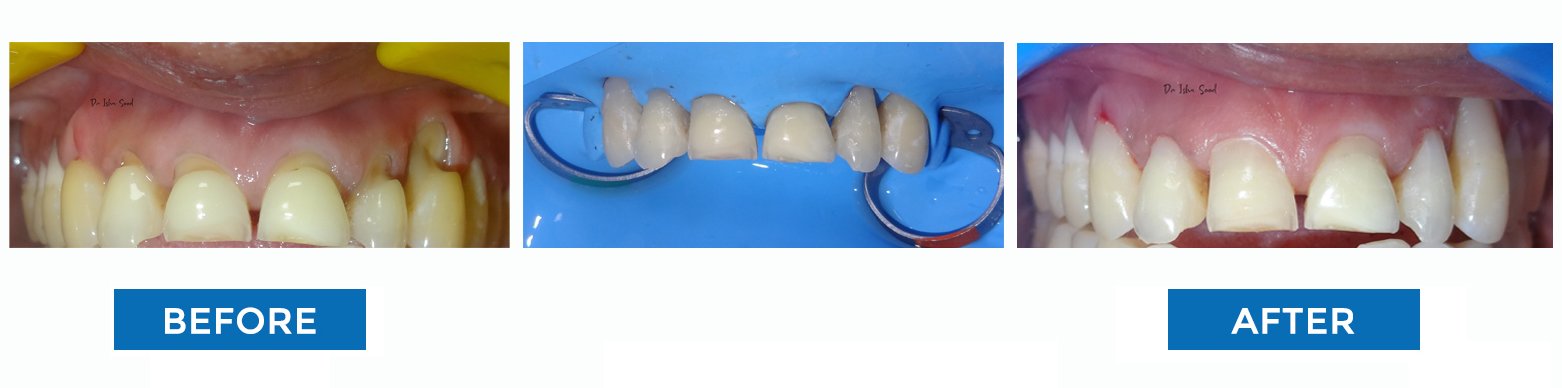

Tooth Coloured Filling (Restoration)

Broken Tooth Repaired with Tooth Coloured Filling

Discoloured Fillings Changed to Tooth Coloured

Aesthetic Filling